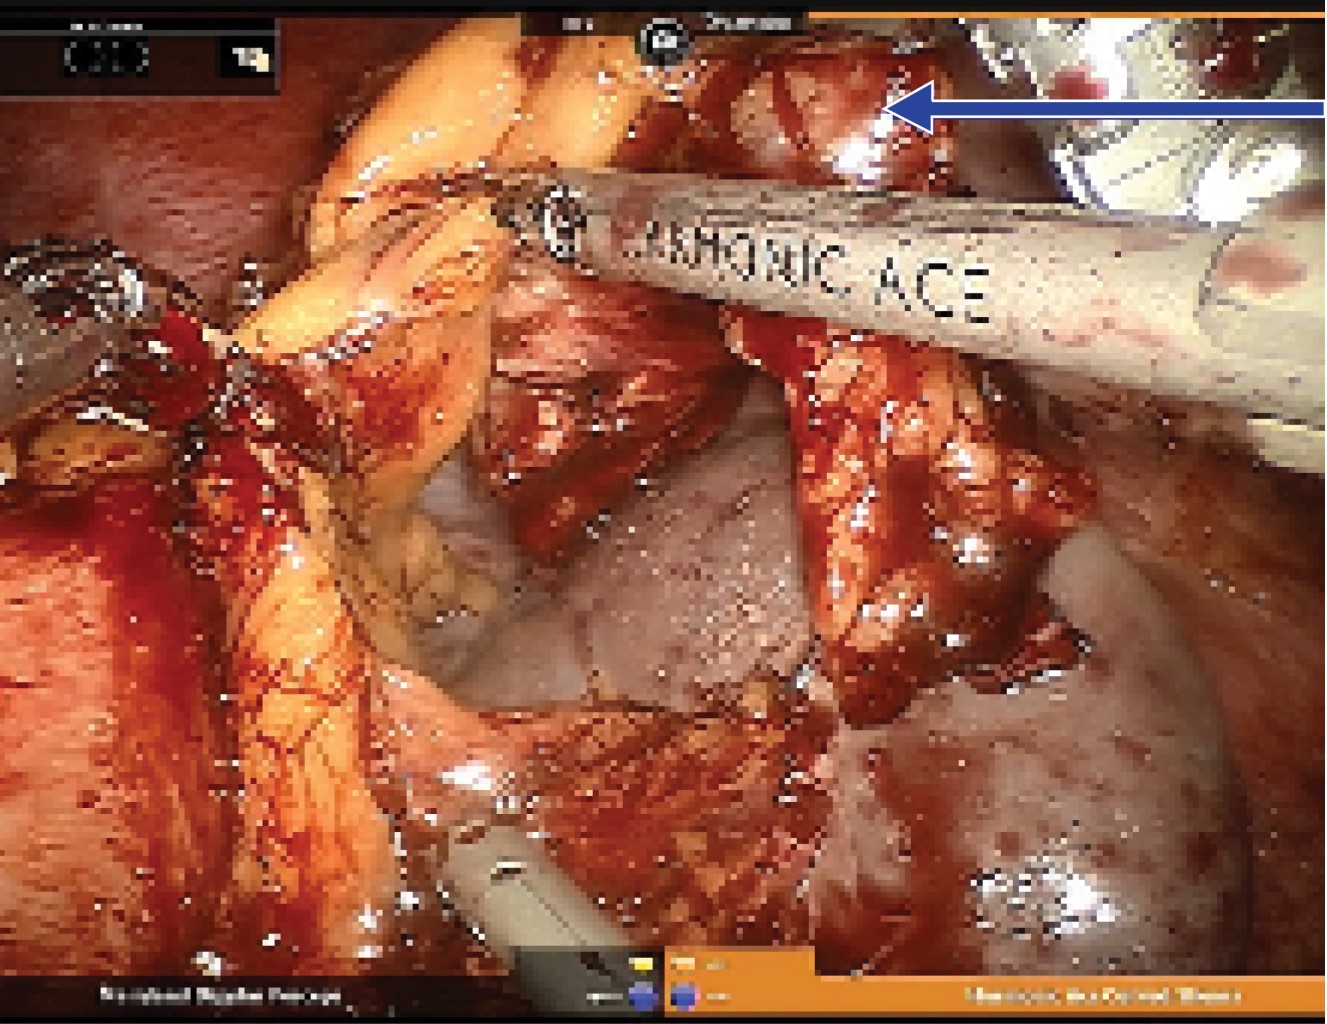

El carro robótico (Da Vinci Si, Intuitive Surgical, Sunnyvale, CA.) se puso en la cabeza del paciente y se llevó a cabo acoplamiento cefálico. Se utilizó disposición de tres brazos como se observa en la Figura 2. El ligamento gastrocólico se seccionó con bisturí ultrasónico y el estómago se retrajo cefálicamente. Se observó lesión subcapsular de alrededor de 2 cm en la cola del páncreas. Mediante sonda de ultrasonido laparoscópico se inspeccionó el páncreas y no se observaron lesiones satélites ni secundarias en la glándula. Con manipulación cuidadosa y disección de los tejidos se creó una ventana retropancreática justo lateral a los vasos mesentéricos, el páncreas se dividió con una engrapadora lineal cortante con cartucho blanco (vascular) de 60 mm, introducida a través del trocar del asistente, la arteria esplénica se disecó mediante bisturí ultrasónico y clips plásticos de polímero vasculares. Debido a su anatomía parcialmente intrapancreática, no fue posible liberar y disecar la vena esplénica del páncreas, por lo que tuvo que ser seccionada con otro cartucho vascular. Para concluir, se resecó la cola pancreática incluyendo la lesión (Figura 3). Se conservó adecuado drenaje venoso del bazo en todos los vasos gastroesplénicos. Se colocó drenaje cerrado cerca del sitio de la sección pancreática. El tiempo de acoplamiento fue de 23 minutos y el de la consola fue de 163 minutos. La pérdida sanguínea se calculó en 200 mL. No se requirieron hemotransfusiones.

Figura 3